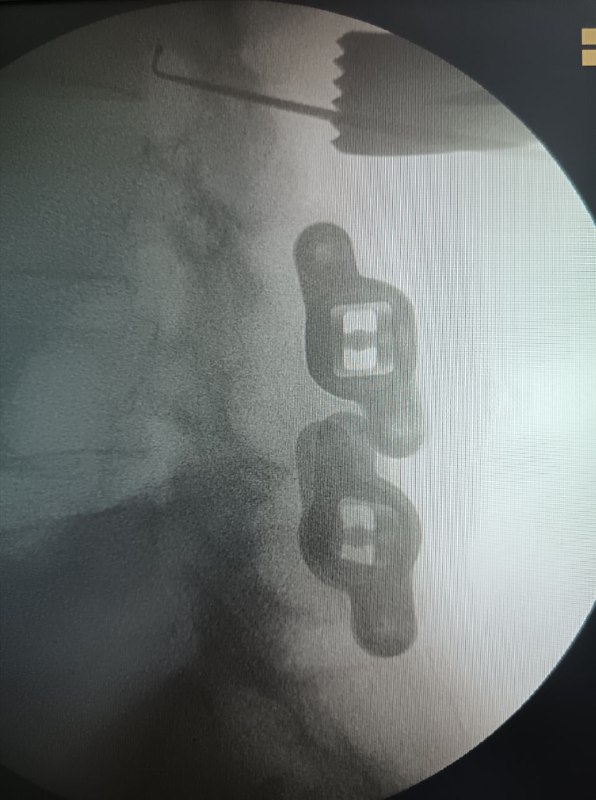

Установка игл Джамшиди перед вертебропластикой

Фото установки игл Джамшиди в тело позвонка перед пункционной вертебропластикой: проколы кожи, рентген‑контроль и последующее введение костного цемента.